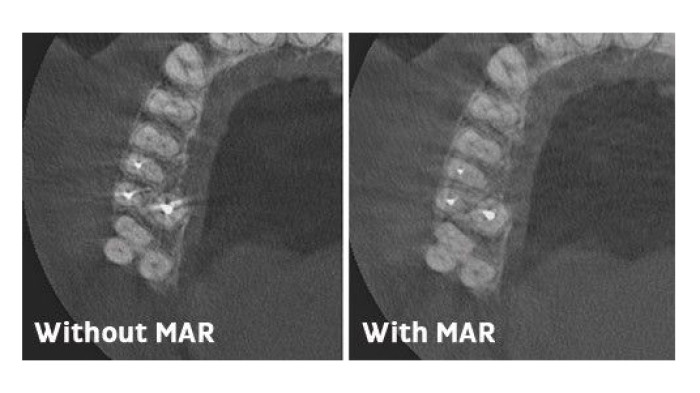

Tydligare bilder med MAR-teknik.

Alternativet för reducering av metallartefakter (MAR) kan väljas av användaren och minskar inverkan av spridd strålning som uppträder i röntgenvolymer med hög densitet. Tekniken optimerar särskilt röntgen av tänder med fyllda rotkanaler.